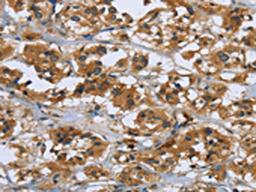

Product & ReviewsAntibodiesRAP1B AntibodyProduct DetailsCat. No.CSB-PA841145TypePrimary AntibodyClonalityPolyclonalHostRabbit0.0/5.0|0 Reviews|Write your own ReviewThe image on the left is immunohistochemistry of paraffin-embedded Human thyroid cancer tissue using CSB-PA841145(RAP1B Antibody) at dilution 1/50, on the right is treated with fusion protein. (Original magnification: ×200)ReviewsSpecificity rating Sensitivity rating Quality rating Be the first to leave a reviewApplications ELISA (ELISA) Western Blotting (WB) Immunohistochemistry (IHC)Antibody OverviewRAP1B Antibody0.0/5.0|0 Reviews